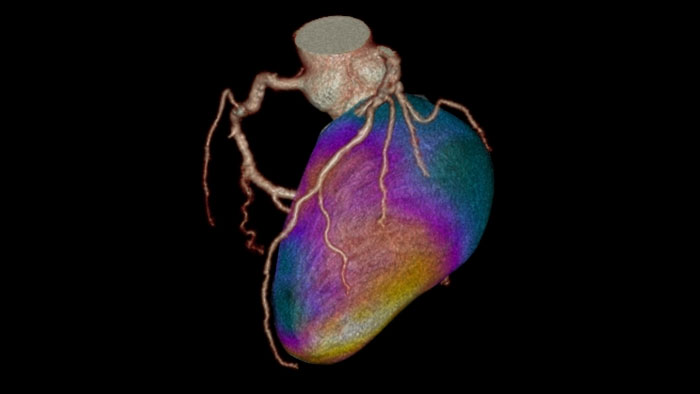

Dynamic Myocardial Perfusion (DMP)

CT Dynamic Myocardial Perfusion (DMP)

Dynamic color maps provide an assessment of myocardial risk

Provides automatic and manual tools to help visualize and assess signal intensity differences (in Hounsfield Unit) focusing on the left ventricular myocardium, providing quantitative myocardial perfusion measurements for CT images.

Benefits

• Supports axial, ECG-gated CTA images, consisting of multiple time shots within the same acquisition of the myocardial region over time (i.e. dynamic CT scans), after an injection of intravenous contrast.

• Automatic and manual tools providing quantitative myocardial perfusion parameters such as: Peak Enhancement, Time To Peak, Perfusion and Blood Volume, and provides color maps representation of the results and graphical representation of intensity curves.